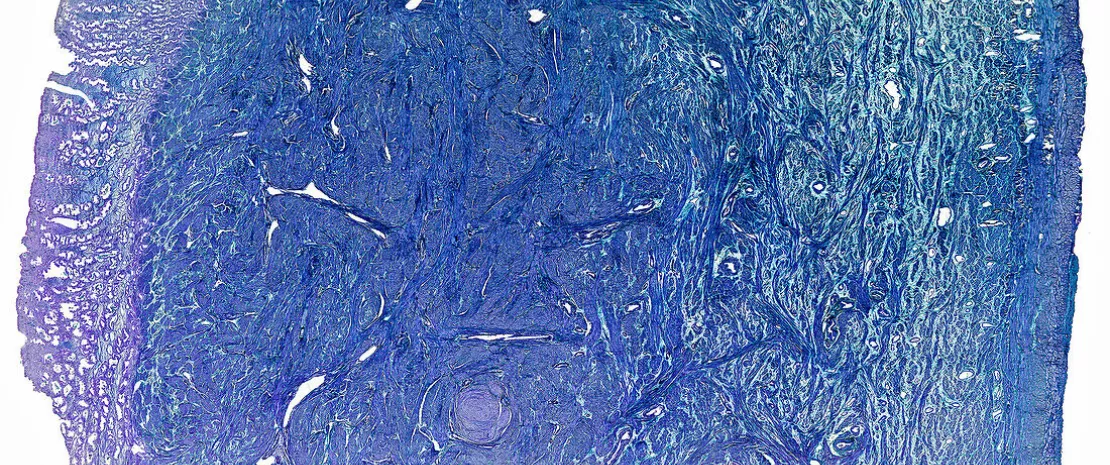

Photo: Endométriose : la piste de l’immunité ouvre de  nouvelles voies de traitement

Endometrioza: podejście ukierunkowane na układ odporności otwiera nowe drogi leczenia

Endometrioza jest związana z zaburzeniami odporności wrodzonej i nabytej, nasilonymi przez dysbiozę endometrium (zaburzenie równowagi mikrobiomu w macicy), która sprzyja stanom zapalnym i progresji zmian. Czy może to prowadzić do wyznaczenia nowych strategii terapeutycznych?